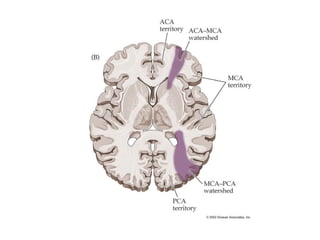

Watershed zones

• Watershed:

– Look at watershed and border zone areas

– Hypo-perfusion

• Location – watershed pattern

• Right hemisphere watershed infarct secondary to

hypoperfusion in the setting of Right ICA stenosis